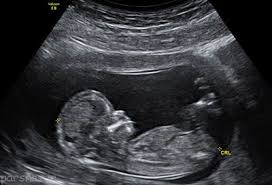

دلایل سونوگرافی جنین

پزشک با استفاده از سونوگرافی میتواند متوجه رشد یا عدم رشد طبیعی جنین شود.

سونوگرافی میتواند برای کنترل حرکت، تنفس و ضربان قلب جنین مورد استفاده قرار بگیرد.